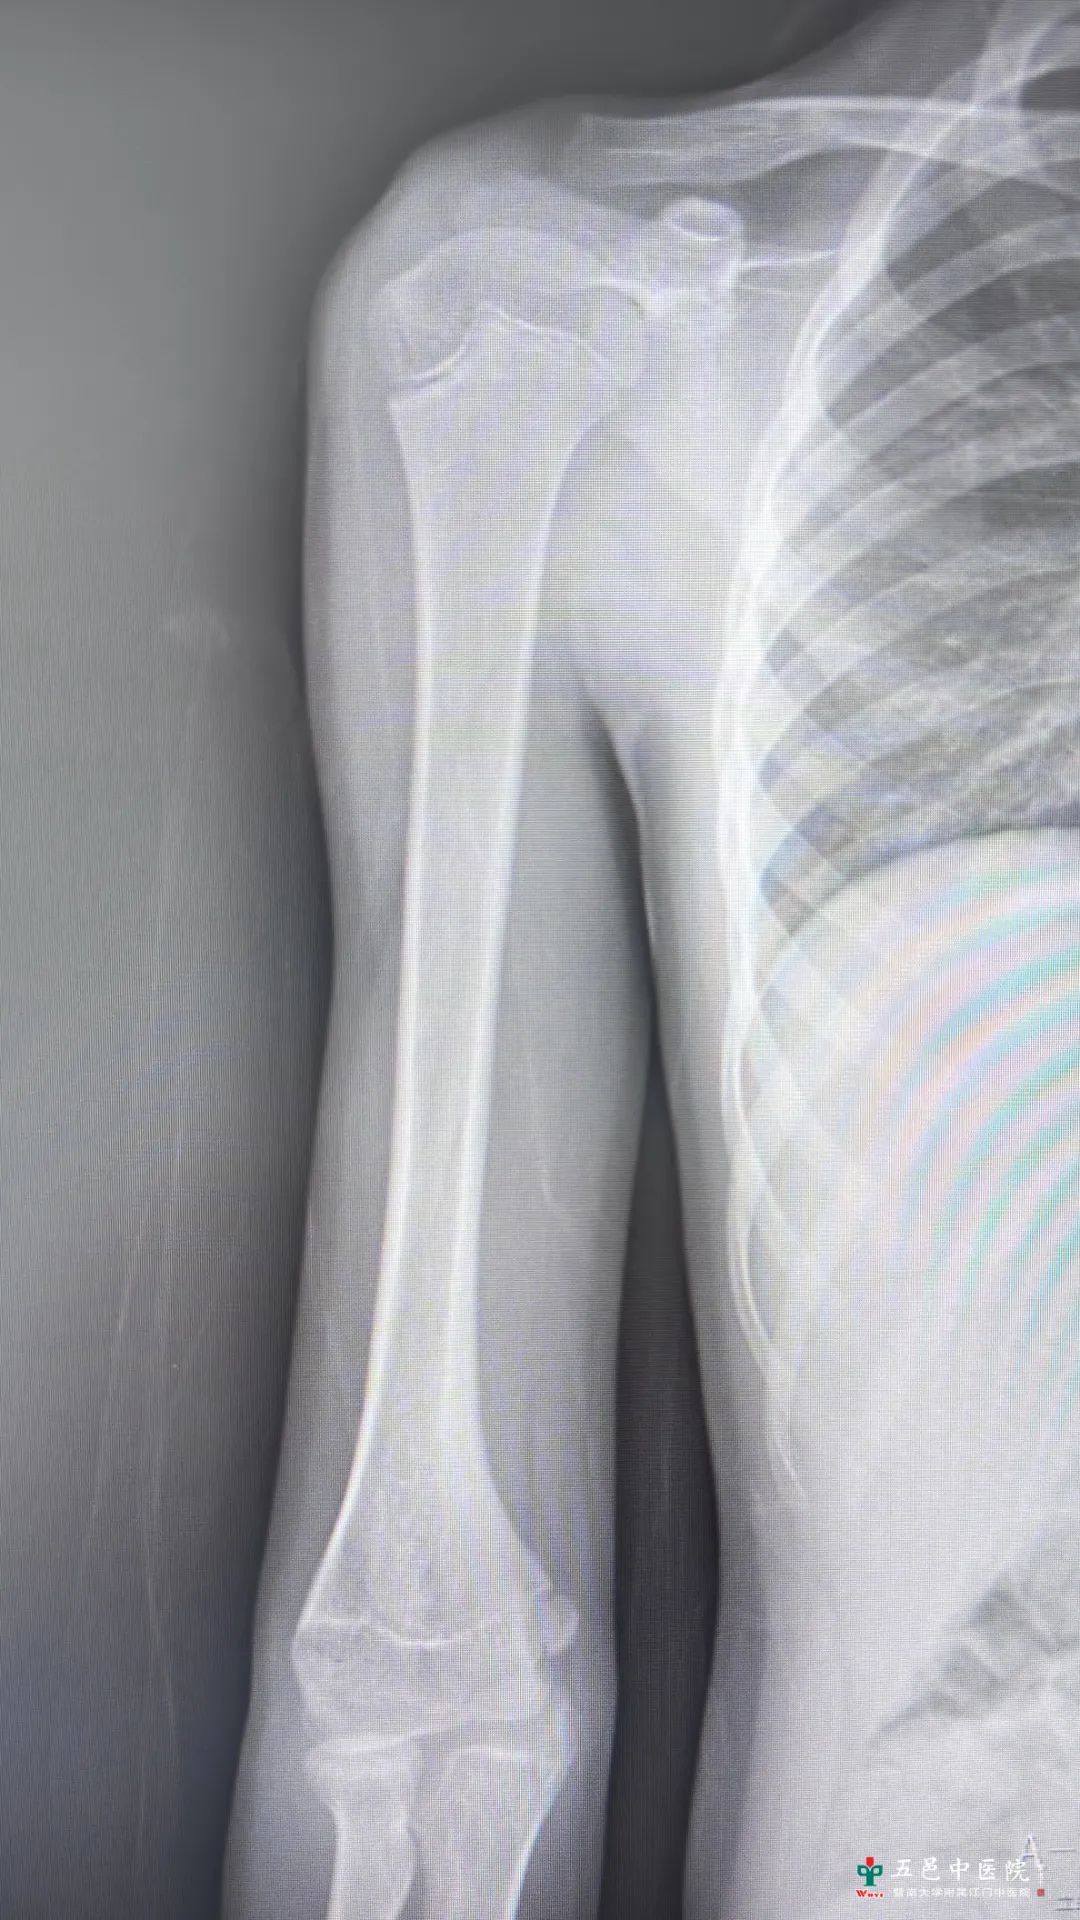

图1-术前正位DR(左)